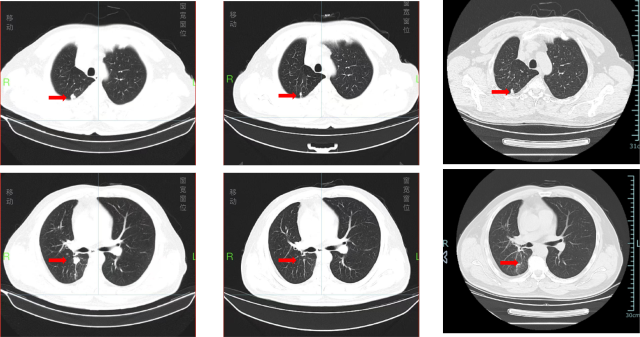

治疗前后的比较(2024.7.10 VS. 2024.10.29 VS. 2025.4.16)